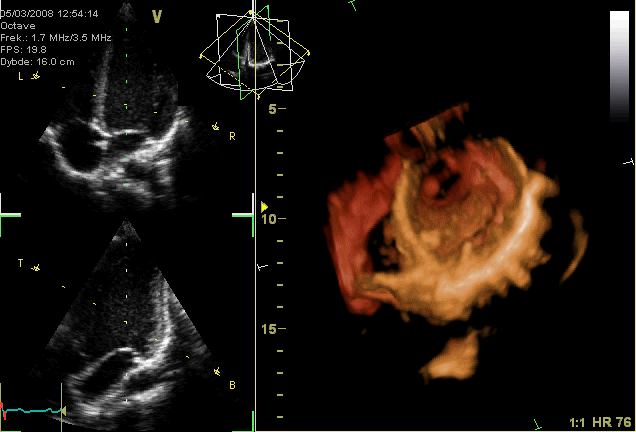

Heart Sounds

Opening and Closing of Heart Valves

The closing of the heart valves generates the "lub, dub" sounds that can be heard though a stethoscope.

"Apikal4D."

http://en.wikipedia.org/wiki/File:Apikal4D.gif Wikipedia CC BY-SA.